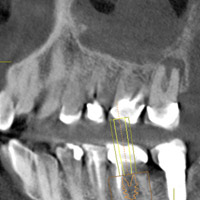

Digital radiography in particular had an immediate impact on Dr. Zuckerberg's practice. "[It was] positive from the get-go," he wrote in an email to DrBicuspid.com. "Having a high-tech office, this technology supported our mission and image, and wowed the patients. They really loved the part about reducing radiation and the fact that there was no additional fee compared to film radiology."

But the most useful aspect he envisioned was an opportunity to present blown-up images of a patient's tooth, instead of tiny film on a viewbox, along with a treatment plan. Once the patients saw the caries in their teeth, it would become a priority for the patient. "My vision was corroborated with a large increase in case acceptance," he noted.